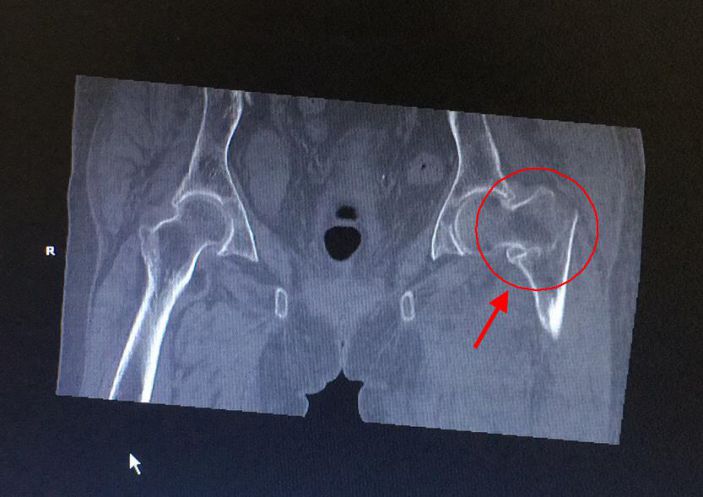

發布時間:2018-03-28 閱讀:3067 3月11日,康美醫院成功爲一名左股骨粗隆間粉碎性骨折的百歲老人開展股骨近端髓内釘(PFNA)内固定手術。

黃婆婆,女,100歲,上塘人,因走路時不慎跌倒,左臀部着地,緻使左髋部疼痛、活動受限,後至某三甲醫院住院治療4天。因高齡,合并有高血壓、老年性退行性心瓣膜病、動脈硬化性腎病、老年性骨質疏松,該醫院不敢爲其手術治療。3月10日,患者轉診至康美醫院外四科(骨科)。